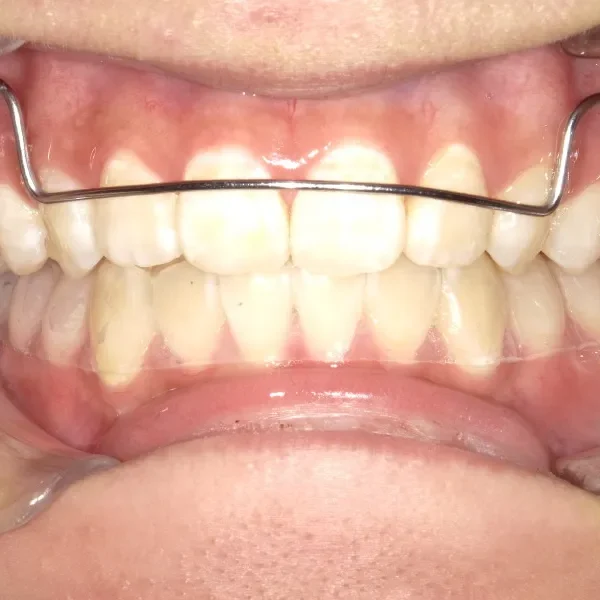

【子供の矯正(一期)】叢生・早期治療・6歳女児【S.T様】

初診時年齢 6歳まで (女性) 主訴 ガタガタ

診断名 叢生 装置名

拡大床

抜歯の有無 非抜歯 治療期間・通院回数 7年 4ヶ月 / 43回

下の歯がずれて生えています。

こどもの歯は下の2本しか抜けていませんが、放っておくとガタガタがきつくなるので、早い段階からの治療としました。

治療回数43回、7年4ヶ月の治療期間で矯正治療を終了しました。

主訴が改善され、ご満足頂きました。

治療終了後